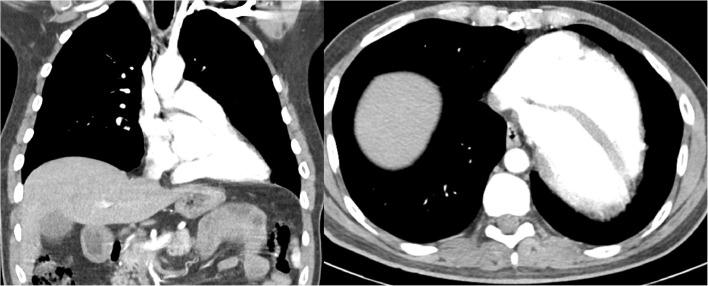

This case report describes a 40-year-old male who presented to the emergency department (ED) with chest pain. Initial diagnostic workup was concerning for a congenital cardiac anomaly, further imaging revealed complete congenital absence of the pericardium (CAP) which is a rare condition. Multimodality cardiac imaging including cardiac computed tomography angiogram (CCTA) was used to confirm the diagnosis of CAP. We briefly discuss various clinical presentations of CAP along with potential complications and other anomalies that could be associated with pericardial agenesis.

本病例报告描述了一名40岁男性,他因胸痛被送往急诊科。初步诊断检查怀疑有先天性心脏异常,进一步的影像学检查显示为完全性先天性心包缺如(CAP),这是一种罕见的病症。包括心脏计算机断层扫描血管造影(CCTA)在内的多模态心脏成像用于确诊CAP。我们简要讨论了CAP的各种临床表现以及可能与心包发育不全相关的潜在并发症和其他异常情况。